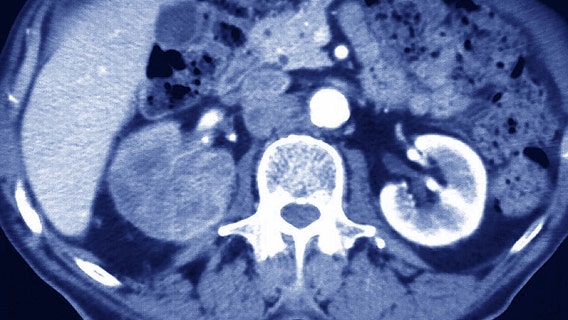

Shannen Doherty, '90210' star, reveals cancer has spread to her brain in emotional video

The "Beverly Hills, 90210" star shared videos of her undergoing a CT scan and finding out her cancer had spread. "The turmoil….. the timing of it all…. This is what cancer can look like."